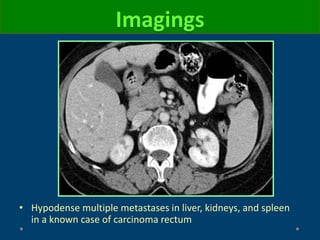

Imagings

CT

• Often nonspecific features

• Multiple solid, hypoattenuating renal masses

○ Typically located in renal cortex or corticomedullary junction

○ Variable enhancement (depend on primary tumor type)

– Hypervascular: Melanoma, breast, neuroendocrine

Heterogeneously enhancing

renal masses with areas of

necrosis due to metastatic

non-small cell lung carcinoma

• Hypodense multiple metastases in liver, kidneys, and spleen

in a known case of carcinoma rectum